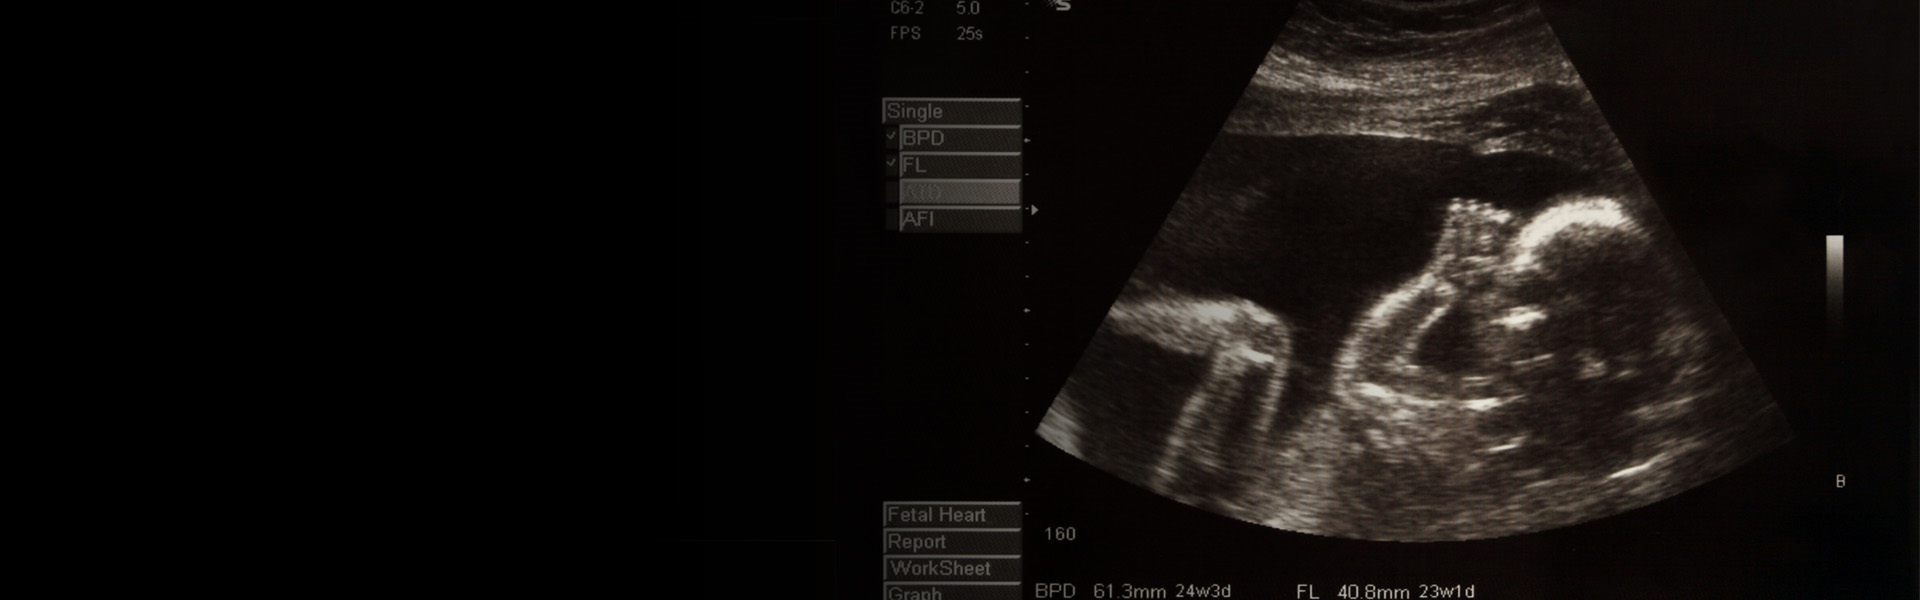

An ultrasound of a baby

The PEEPO project aims to explore the associations between adversities experienced in the prenatal period and children’s later cognitive development and educational attainment. A series of reviews will be undertaken to explore specific adversities, including topics such as maternal stress, maternal malnutrition, teratogens and drugs, maternal sleep, and maternal metabolic disorders. The aim of the project is to better inform policy by examining which factors are important in pregnancy for influencing children’s later achievement. It will therefore enable effective recommendations for maternal care that stand to improve children’s chances of strong educational outcomes from the outset. The project will bring together research across disciplines for a better understanding of what we know, and crucially, what we need to know next, about the effects of adversity during pregnancy on long-term educational outcomes.